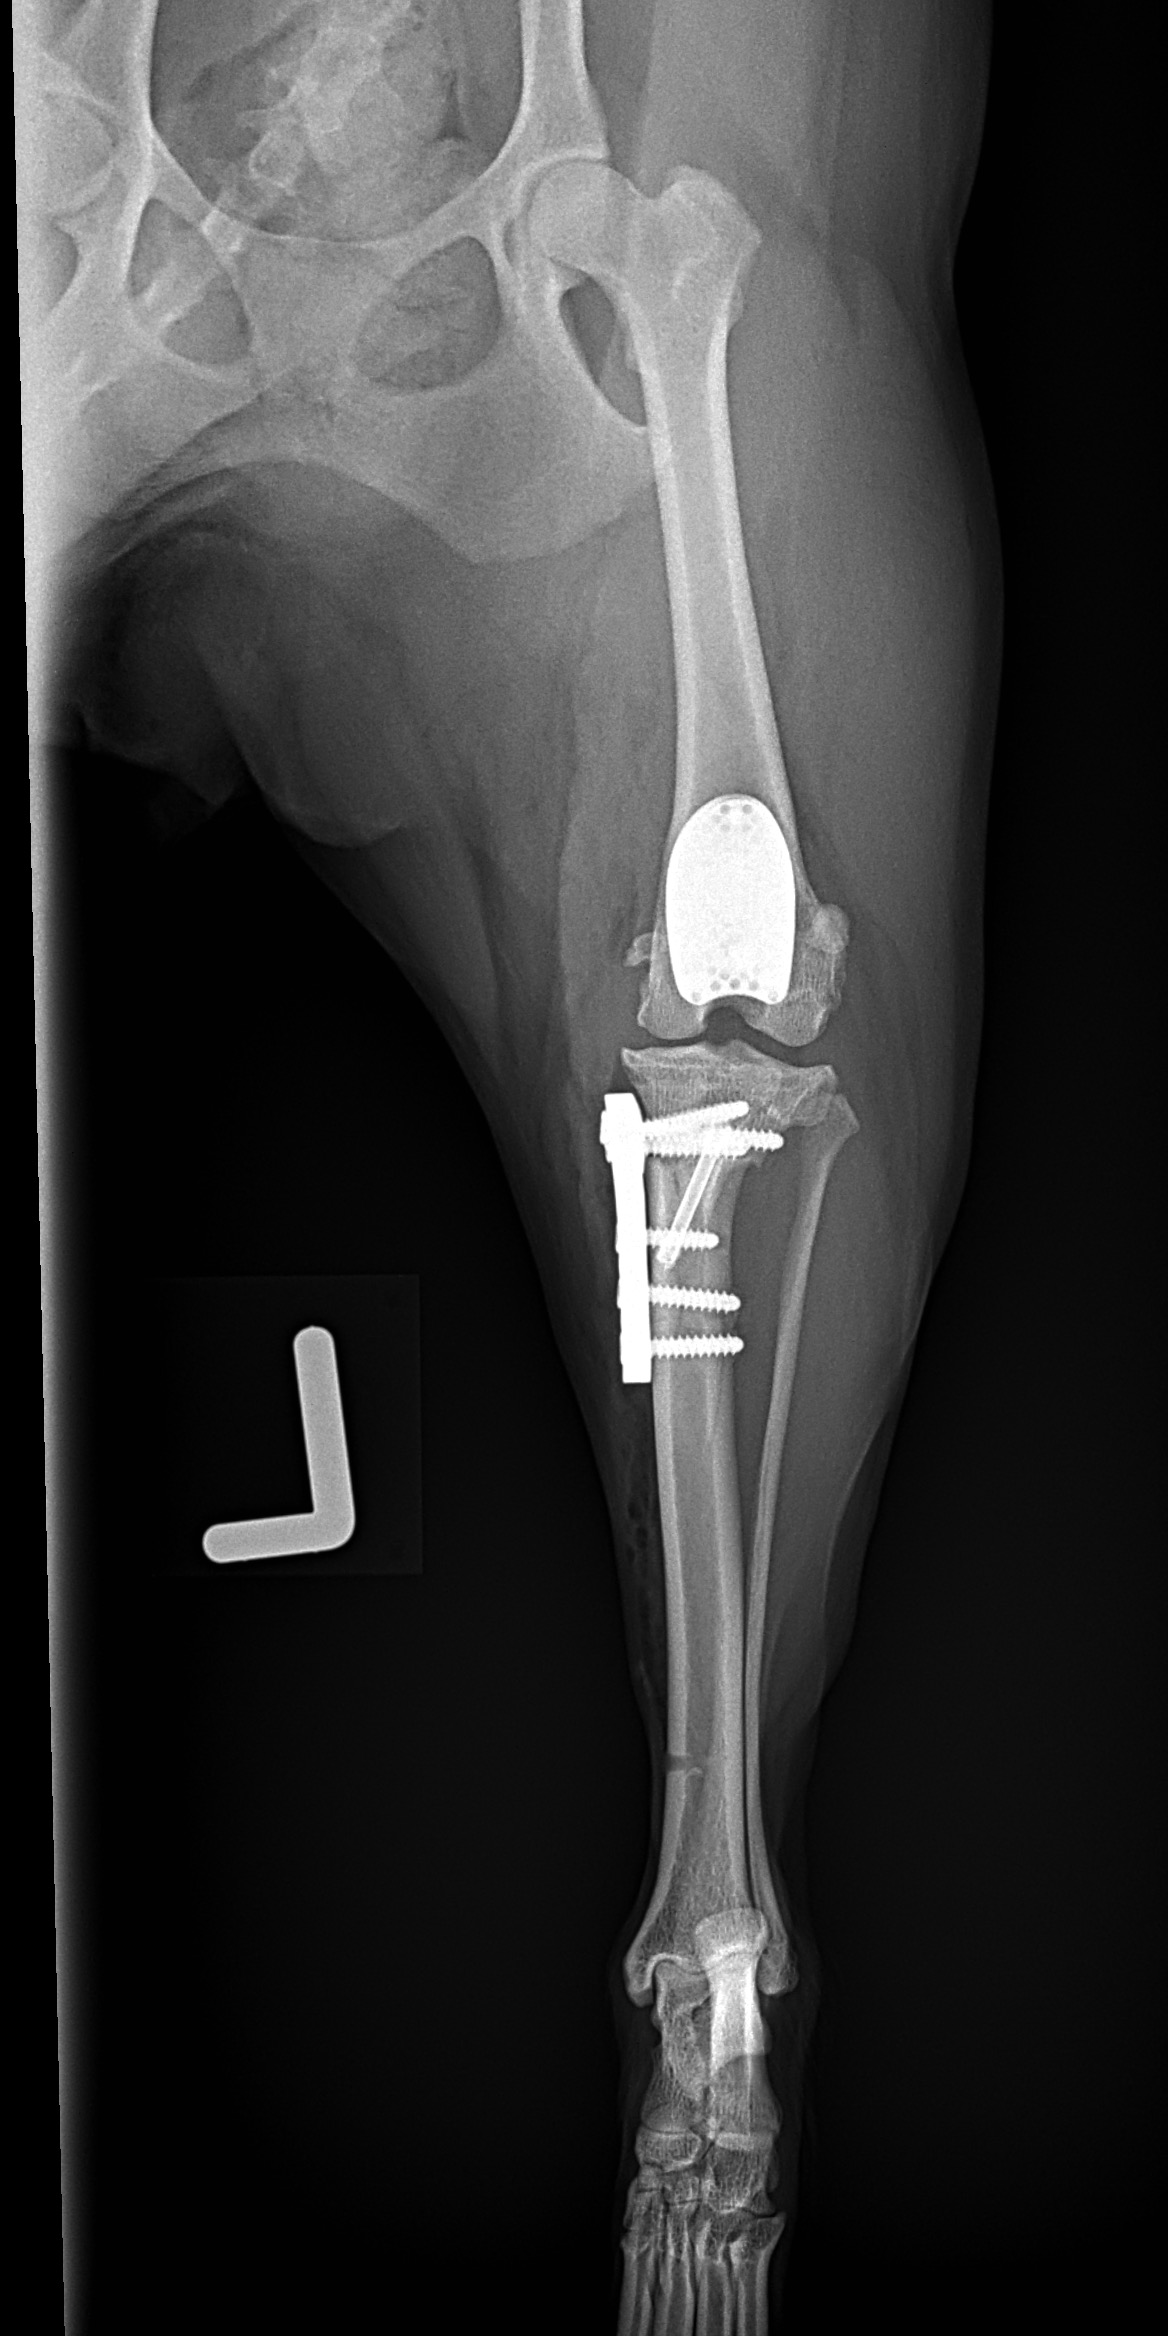

膝蓋骨内方脱臼に罹患していたワンコが急に跛行するようなったとの事。前十字靭帯断裂の併発です。大腿骨滑車は形成されておらず、大腿骨遠位にOAが生じています。人工滑車置換術とCBLOで除痛と機能回復を目指します。しばらくは安静が必要です。